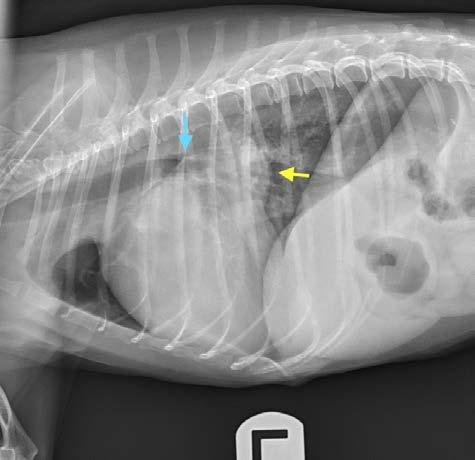

El CPV interrumpe el recambio normal celular del intestino delgado, produciendo acortamiento y atro fia de vellosidades, que pierden la capacidad de ab sorción, causando enteritis profunda, con vómitos, diarreas hemorrágicas (Fig. 2), malabsorción y trans locación bacteriana por ruptura de la integridad de la barrera intestinal (aumenta el riesgo de septicemia por E. coli).1,2,4-6,15 Otros signos clínicos son anorexia, depre sión, fiebre, pérdida de peso y deshidratación.

Figura 1. del parvovirus canino. Figura 2. Diarrea hemorrágica en un paciente canino con parvovirus.

Diagnóstico por imagen Los hallazgos no son específicos de pacientes infecta dos con parvovirus. Las radiografías abdominales pue den ser normales al inicio de la enfermedad, o mostrar signos de íleo con distensión de asas intestinales por acúmulo de líquido o gas. Los signos ecográficos son asimismo inespecíficos, mostrando áreas de distensión con fluido y gas tanto en estómago como en intestino, íleo con movimientos peristálticos inefectivos, efusión peritoneal anecoica, etc.1,2,5,6 Ambas técnicas ayudan a descartar otras causas del cuadro clínico, como son cuer pos extraños, obstrucción e invaginación intestinal.1,2,5,6

Figura 3. Medición de la presión arterial no invasiva mediante un méto do oscilométrico en un paciente canino con parvovirus. Figura 4. Medidas de bioseguridad para evitar la propagación intra hospitalaria del parvovirus: uso de bata, guantes, calzas y material ex clusivo para estos pacientes. Figura 5. Infección del punto de inyección por catéter intravenoso, con necrosis de la piel y presencia de contenido purulento, en un paciente canino leucopénico por parvovirus. Figura 6. Radiografía de tórax laterolateral de un paciente canino tras la inserción de un catéter venoso central para comprobación de la co rrecta colocación (vena cava craneal).